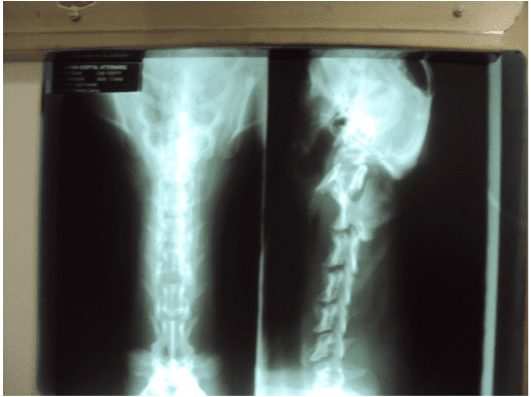

Canino, macho, raça Teckel, com 12 anos. Em 15/02/2011 foi atendido, apresentando a perda de propiocepção de membros anteriores e diminuição dos reflexos, não estava caminhando. Foi solicitado radiografia de região cervical. Foram observadas áreas de calcificação e diminuição do espaço intervertebral entre C2C3, e C5 e C6. Animal foi tratado inicialmente com fármacopuntura (vitamina B12), sendo ainda prescrito [1]Prednisona 20 mg SID por dez dias e eletroacupuntura em dias alternados. Dois dias após o cão havia apresentado melhora clinica e voltou a andar. Foi recomendado eletroacupuntura duas vezes por semana, [2]cloridrato de Tramadol e [3]Carprofeno 25 mg BID. No início de março o animal parou de andar novamente, apresentava sensibilidade na coluna cervical e emagrecimento, o proprietário pediu a Eutanásia. Durante a reavaliação o animal apresentou dor nos membros e diminuições dos reflexos nos membros anteriores. Foi internado para retomar o tratamento com acupuntura, analgésico e antiinflamatório. Após 15 dias de tratamento o animal estava pior. Ficava deitado e não levantava a cabeça e o tronco, iniciou anorexia. Dois dias após, foi suspenso todo o tratamento que estava sendo feito. Iniciou-se o tratamento com o uso do medicamento homeopático [4]Homeopet Pró-coluna® (Calcium fluoricum 10-30, Solanum malacoxylon 10-10,Causticum 10-24, Hypericum perforatum 10-60, Hekla lava 10-24, Apis mellifica 10-24, Plumbum metallicum 10-60, Nux vomica 10-14) 2 borrifadas 3 vezes ao dia.

Radiografias de região cervical. É possível se observar áreas de calcificação e diminuição do espaço intervertebral entre C2-C3, e C5 e C6.